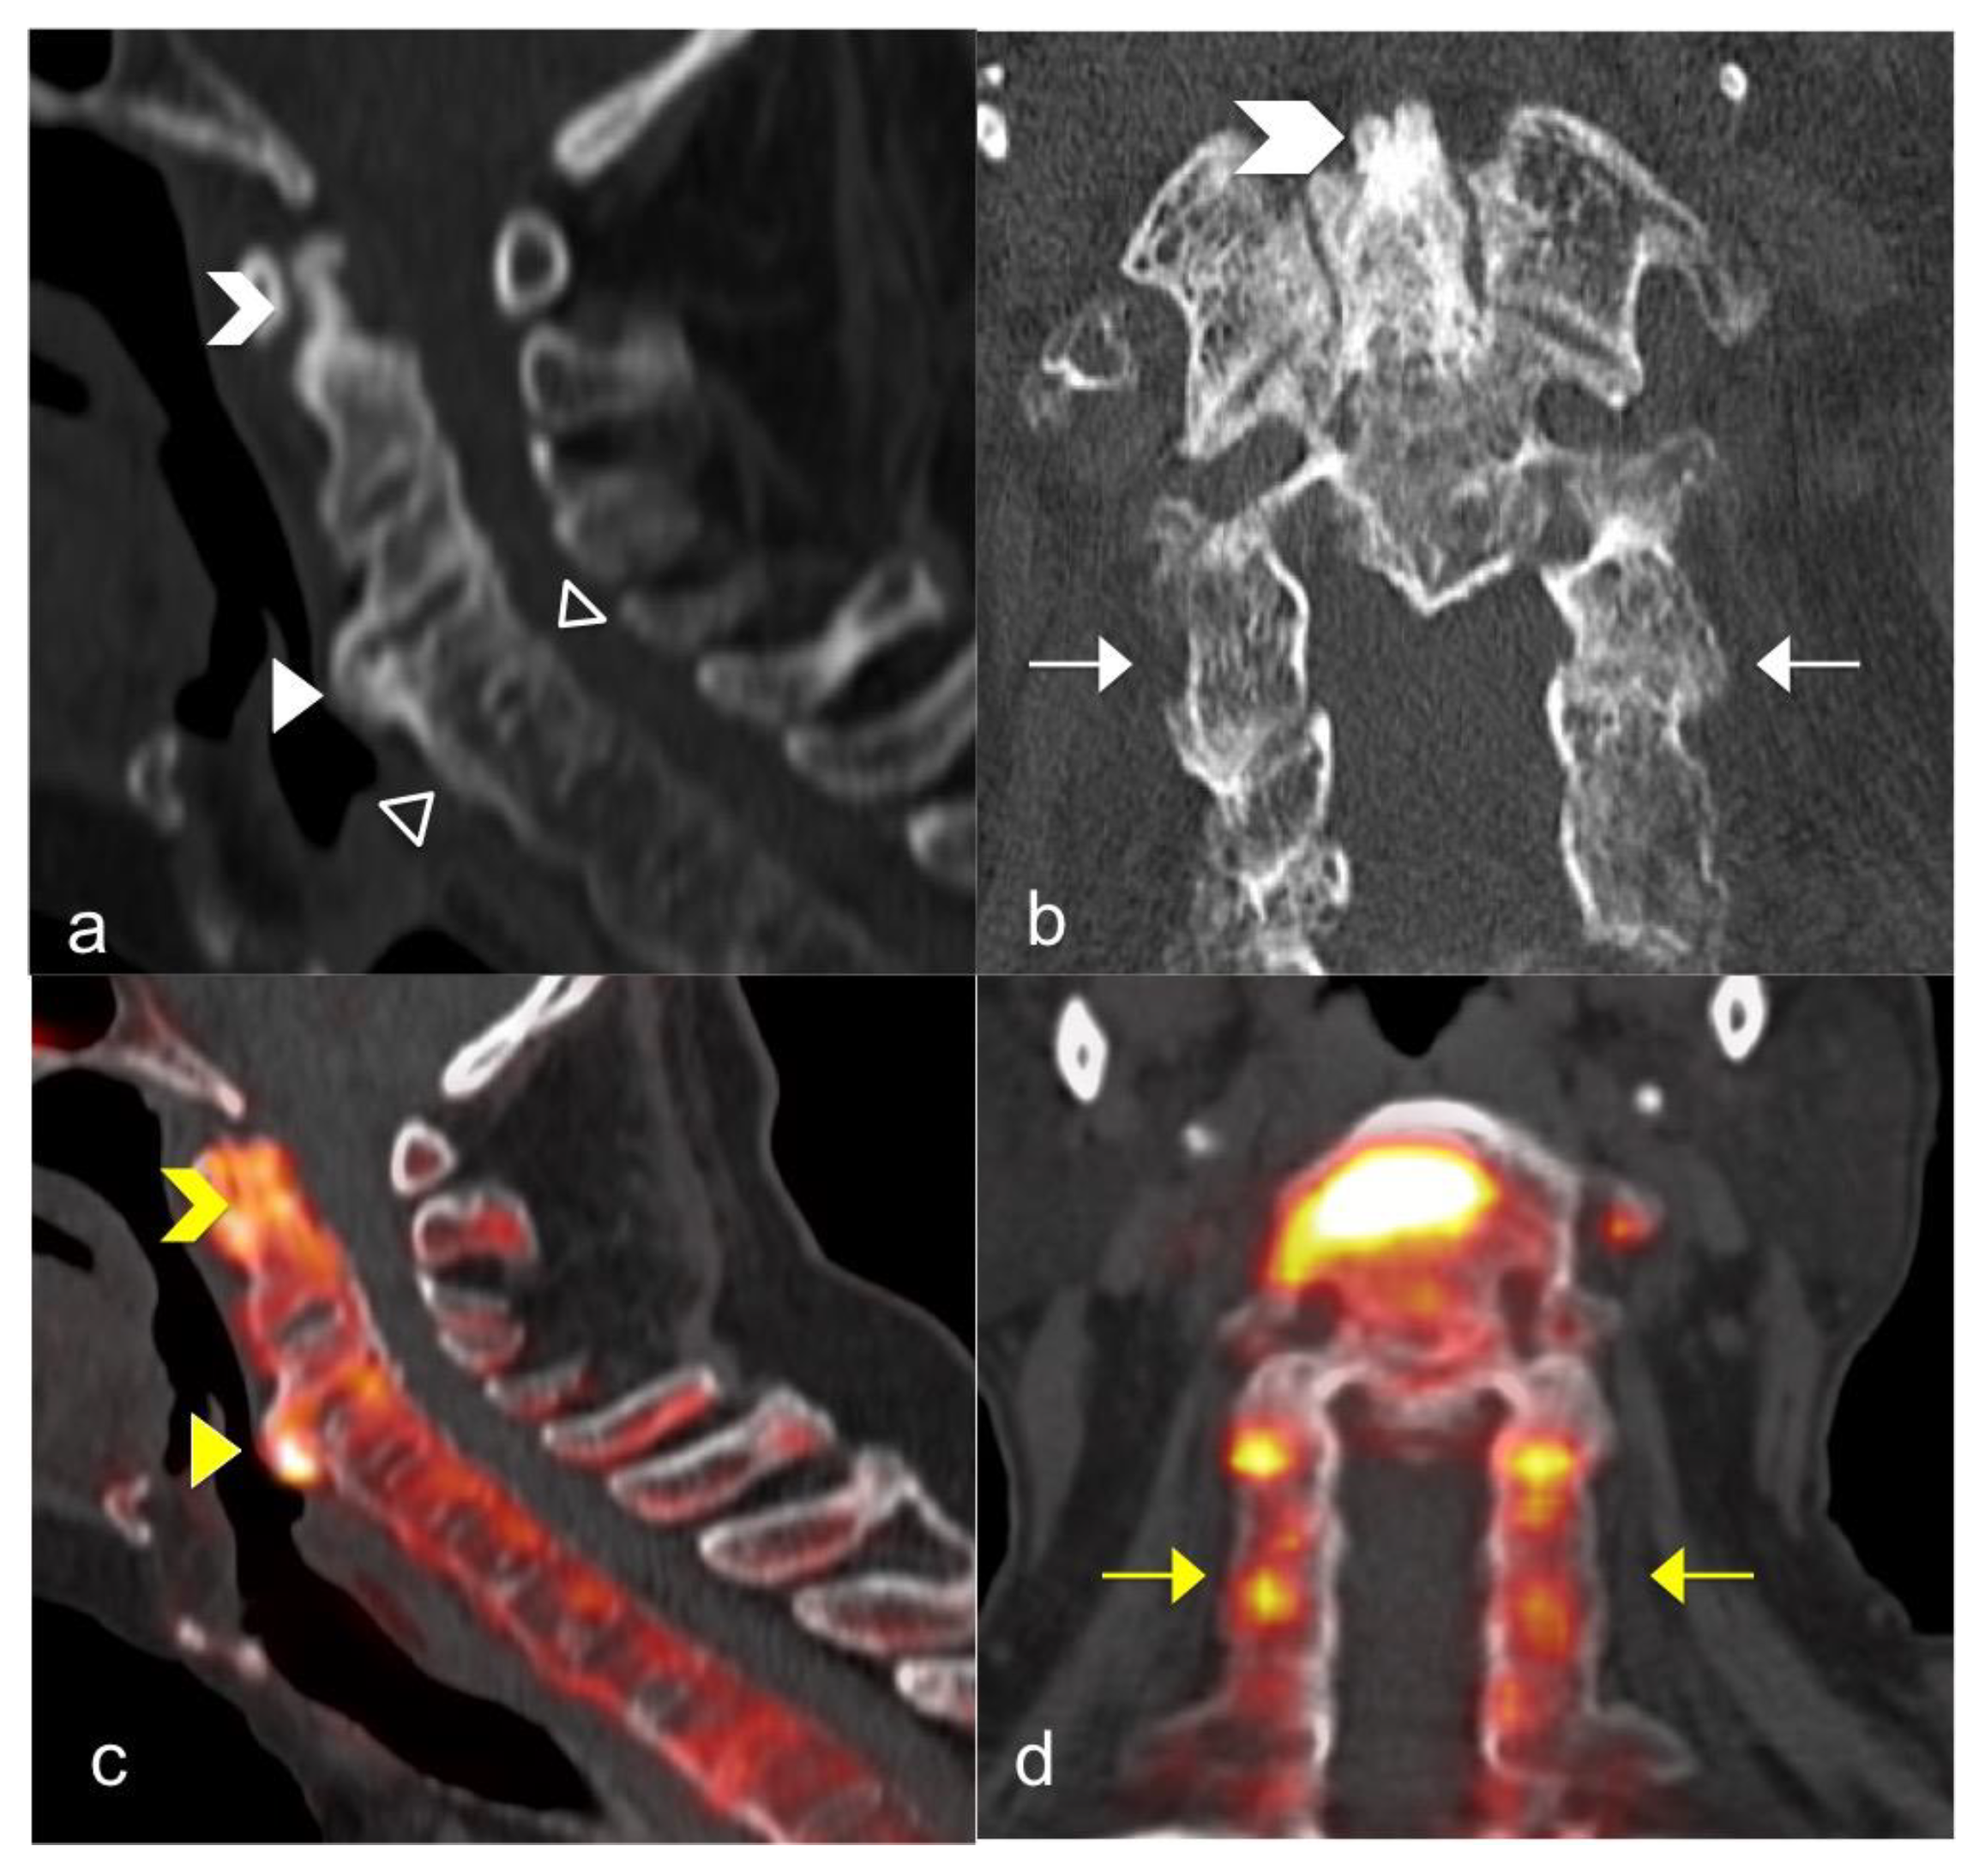

3.3. FNa 18 PET CT

- Raynal, M.; Bouderraoui, F.; Ouichka, R.; Melchior, J.; Morel, O.; Blum, A.; Chary-Valckenaere, I.; Ngueyon Sime, W.; Roch, V.; Maksymowych, W.; et al. Performance of 18F-sodium fluoride positron emission tomography with computed tomography to assess inflammatory and structural sacroiliitis on magnetic resonance imaging and computed tomography, respectively, in axial spondyloarthritis. Arthritis Res. Ther. 2019, 21, 119. [Google Scholar] [CrossRef] [Green Version]

- Son, S.M.; Kim, K.; Pak, K.; Kim, S.-J.; Goh, T.S.; Lee, J.S. Evaluation of the diagnostic performance of 18F-NaF positron emission tomography/computed tomography in patients with suspected ankylosing spondylitis according to the Assessment of SpondyloArthritis International Society criteria. Spine J. 2020, 20, 1471–1479. [Google Scholar] [CrossRef] [PubMed]